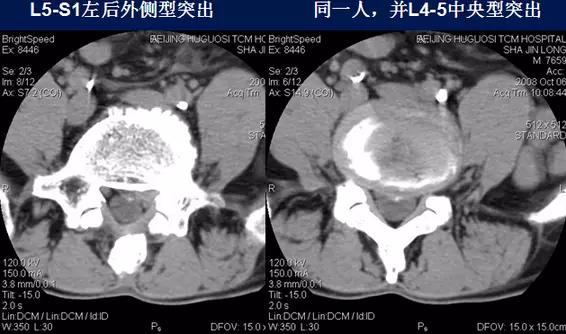

椎间盘突出:

⑴中央型:椎间盘影局限性超出椎体边缘,硬膜囊可受压,硬膜外脂肪间隙变窄、消失,可伴纤维环钙化。

⑵旁中央型:椎间盘影局限性超出椎体边缘,神经根受压。

⑶后外侧型:椎间盘影于椎间孔方向局限性超出椎体边缘,神经根受压,椎间孔、侧隐窝变窄。